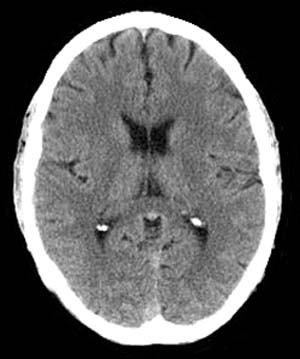

Radiographically Pick's disease, a variant of Frontotemporal dementia, appears as prominent atrophy of the temporal and/or frontal lobes on CT. Sulcal prominence, widening of the Sylvian fissure with atrophy of the insula, inferior frontal and superior temporal lobes, as well as enlargement of the frontal or temporal horns of the lateral ventricles is most evident on MRI. In addition, MR volumetric analysis may show subtle involvement of the orbitofrontal cortex.

![]() ![]() The images above are axial Head CT scans. |